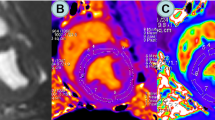

Left ventricular (LV) volume profiles of control and diabetic rats obtained from MRI reconstruction of LV slices collected throughout the complete cardiac cycle Graphical representation of LV volumes corresponding to ten equally incremented phases of the rat cardiac cycle is provided. The LV volumes for control (open circles) and diabetic (filled circles) rats were computed from the corresponding MRI scans as described in methods. End-diastole and end-systole correspond to phase 1 and phase 6, respectively, in both the control and diabetic group. LV volumes in all but phases 4 and 5 were significantly different (*, P < 0.05) between groups. Note that the actual cardiac cycle duration was 216.7 ± 28.7 ms in control and 242.5 ± 15.0 ms in diabetic rats, with an insignificant difference (P > 0.05). Hence the cardiac cycle was divided into phases 1 through 10 as discussed in the methods section.

The first derivatives of the LV volume with respect to time (dV/dt) during the cardiac cycle phase transitions are presented in Figure 3. The dV/dt values remained significantly different (P < 0.05) between the control and diabetic groups at all but the phase 6–7 (the end-systolic phase) transition suggesting a phase sensitive flow velocity difference between control and diabetic LV in this particular model of DCM.

Cardiac cycle left ventricular (LV) dV/dt values for control and diabetic rats First derivatives of LV volume with respect to time for control (open bars) and diabetic (filled bars) rats obtained from slopes of secant lines connecting the subsequent phases of cardiac cycle are presented. The x-axis labels refer to phase transitions during the cardiac cycle (for example, '1' corresponds to phase 1–2 transition). The negative dV/dt values correspond to systole and positive values correspond to diastole. The dV/dt values corresponding to all transitions except 6–7 (the end-systolic phase transition) were significantly different between control and diabetic rats (*, P < 0.05).